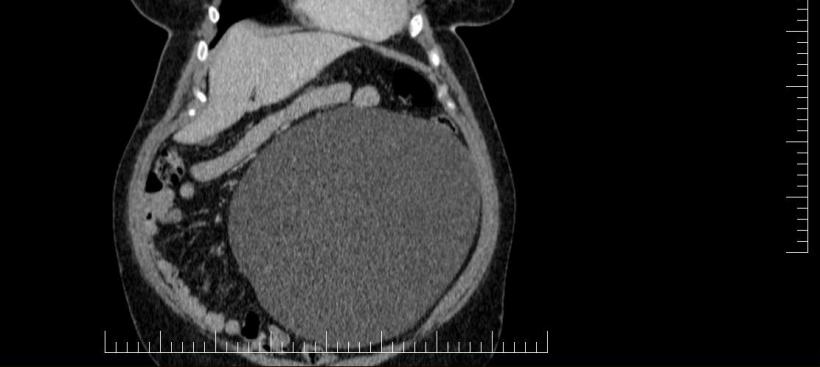

Performanță medicală la Sibiu: Chist ovarian de 4,5 kilograme, extirpat cu succes de la o pacientă | Galerie Foto | Imagine 3

Spitalul Militar de Urgență „Dr. Alexandru Augustin” Sibiu